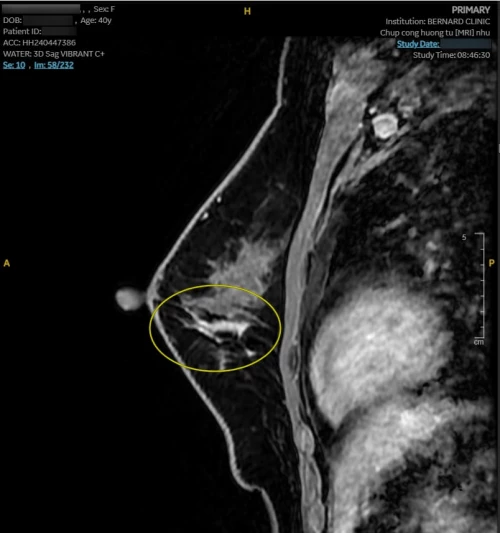

Hình ảnh MRI cho thấy nhiều bất thường. Vú phải có nang vú vị trí 6 giờ, cách núm vú 3cm, d-7mm, phân loại BI-RADS 2. Vú trái có bất thường tín hiệu diện rộng 1/2 dưới (6 - 8 giờ), giới hạn bờ kém rõ, tổn thương dạng đám/nốt/đường, BI-RADS 4.

| Hình ảnh tổn thương qua MRI với Coil Nhũ chuyên biệt, chụp tại Bernard Healthcare |

Nhận thấy hình ảnh MRI bất thường, Hội đồng Y khoa Bernard lập tức chuyển hội chẩn “second opinion” với các Giáo sư Chẩn đoán hình ảnh của Bệnh viện Đại học Yamanashi (Nhật Bản). Kết luận từ chuyên gia Nhật tương đồng: tổn thương trong ống tuyến - nghi ung thư tại chỗ (carcinoma in situ), BI-RADS 4B.